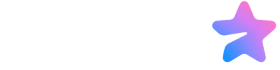

میگزوم قلبی یک تومور است که بر قلب تاثیر میگذارد. این شایعترین تومور غیرسرطانی اولیه قلب است. اندازه میگزومها متغیر است. برخی از آنها به اندازه 1 سانتیمتر قطر دارند، در حالی که برخی دیگر میتوانند تا 15 سانتیمتر رشد کنند. حدود 74% از تمام میگزومها در دهلیز چپ، که اتاق بالایی سمت چپ قلب است، ایجاد میشوند. حدود 18% در دهلیز راست شکل میگیرند. بیشتر میگزومها به عنوان میگزومهای دهلیزی شناخته میشوند زیرا در اتاقهای بالایی قلب ایجاد میشوند. باقیمانده (8%) در بطنها (اتاقهای پایین قلب) شکل میگیرند.

میگزومها معمولاً از سپتوم دهلیزی رشد میکنند. این دیواره عضلانی است که دهلیز چپ و دهلیز راست را از هم جدا میکند. آنها معمولاً با یک پدیکل (پایهای که اجازه میدهد میگزوم حرکت کند) به سپتوم متصل میشوند. تومور میتواند حرکت کرده و گاهی به یکی از دریچههای قلب بیفتد و باعث مشکلات در جریان خون شود.

• انسداد دریچه: میگزومها معمولاً روی یک پایه رشد میکنند و هنگام عبور خون از داخل اتاق قلب به جلو و عقب حرکت میکنند. اگر یک میگزوم وارد دهانه یک دریچه شود، میتواند جریان خون از طریق آن دریچه را به طور موقت مسدود کند. این اغلب در دریچه میترال اتفاق میافتد که دهلیز چپ و بطن چپ را به هم وصل میکند. این فرآیند «پلاگ و جدا شدن» میتواند باعث اختلال در انتقال خون به طور یکنواخت از طریق قلب و به بدن شما شود.